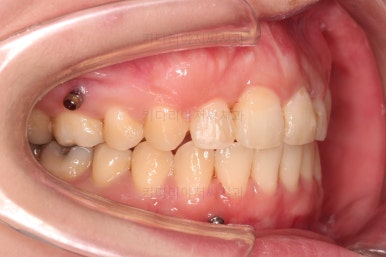

장치를 구성합니다.

이번 환자분은 윗니는 세라믹, 아랫니는 메탈 장치를 선택하셨는데요.

둘 다 물론 자가결찰 장치였고요.

동일한 제품의 장치이므로 혼용해서 쓰는게 가능합니다.

많이 보이는 부분은 세라믹, 잘 안보인다고 여겨지시는 부분은 메탈로 선택하면서 치료비 측면도 함께 고려한거죠.

장치 부착 직후의 모습인데요.

보이는 느낌과 장치 때문에 약간 더 튀어나오는 입매 참고 바랍니다.